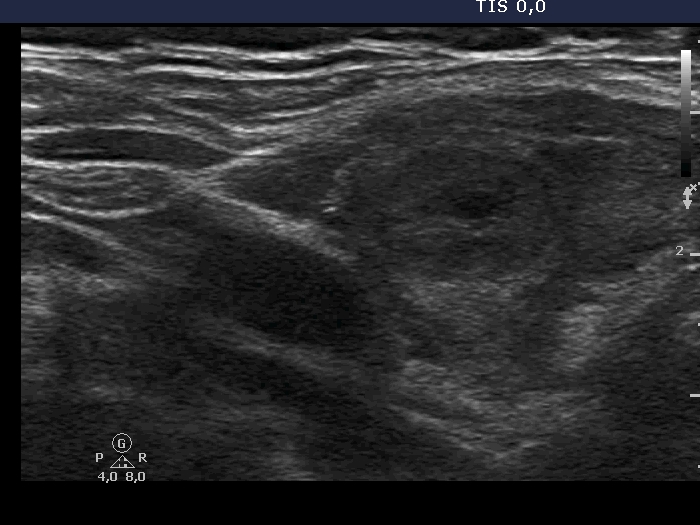

Examination in 2018 (second row of images):

Clinical data. The patient came to a routine follow-up. She had no complaints.

Palpation: unchanged.

Laboratory test: TSH 0.36 mIU/L on daily 125 microgram levothyroxine.

Ultrasonography. Except for the lesion which was previosuly cytologically investigated, the pattern remained unchanged. The lesion in question became cystic and was composed of two chambers. In the tissue part separating the two chambers, hyperechoic granules have appeared. These were mostly related to ventral cystic areas, therefore, they should be regarded as back wall figures.

We recommended that she takes the replacement therapy at the same dose and has a TSH scan after half a year and an ultrasound scan after two years.